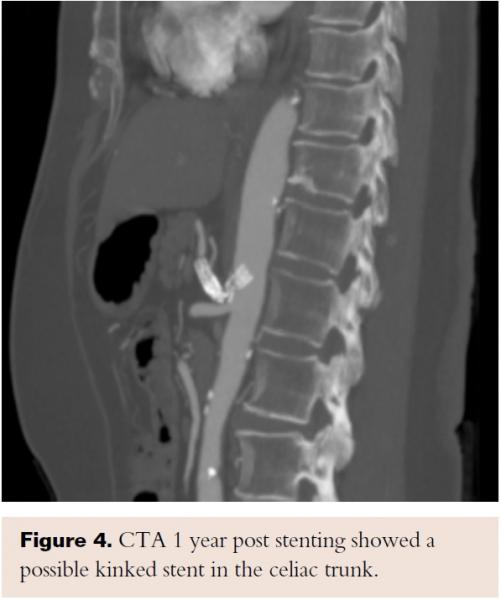

A few days after the procedure, the patient’s gastrointestinal symptoms started resolving; first, her pain was completely gone and then her appetite started to improve. At 1-year follow-up, she remained asymptomatic and regained 25 lb. Repeat CTA for right upper-quadrant pain and elevated lactic acid showed a significant distention of the common bile duct and mild intrahepatic biliary duct dilatation. The CT angiogram also showed a possible kinked stent in the celiac trunk; however, the enhancement of the distal celiac branches were consistent with patency and the patient stayed asymptomatic after the biliary stasis episode resolved (Figure 4). At 2-year follow-up exam, she had maintained her normal weight and remained completely asymptomatic.